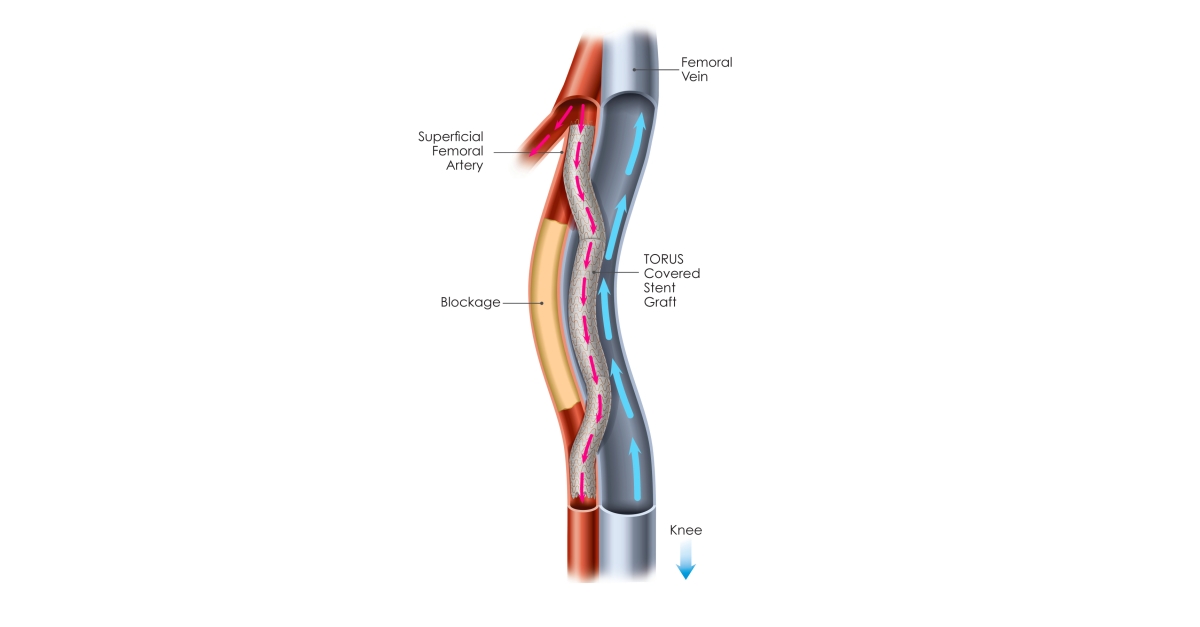

PQ Bypass gets FDA breakthrough device status for Detour System

PQ Bypass Announces CE Mark for DETOUR Percutaneous Bypass Technologies

PQ Bypass study meets safety efficacy endpoints MassDevice

PQ Bypass Incorporated docx 1 PQ Bypass Incorporated Performance

PQ Bypass Receives FDA Breakthrough Device Designation for the World

PQ Bypass Receives FDA Breakthrough Device Designation for the World

PQ Bypass Announces 60 Million Financing to Advance New Therapeutic

PQ Bypass Earns Frost amp Sullivan s European Technology Innovation Award

PQ Bypass Announces New President And CEO Medical Product Outsourcing

PQ Bypass Announces 60 Million Financing to Advance New Therapeutic